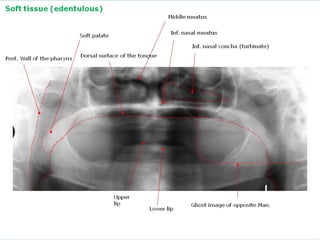

Soft tissue (edentulous)

Middle meatus

Inf. nasal meatus

Soft palate

Inf. nasal concha (turbinate)

Post. Wall of the pharynx

Dorsal surface of the tongue

Upper

lip

Lower lip

Ghost image of opposite Man.